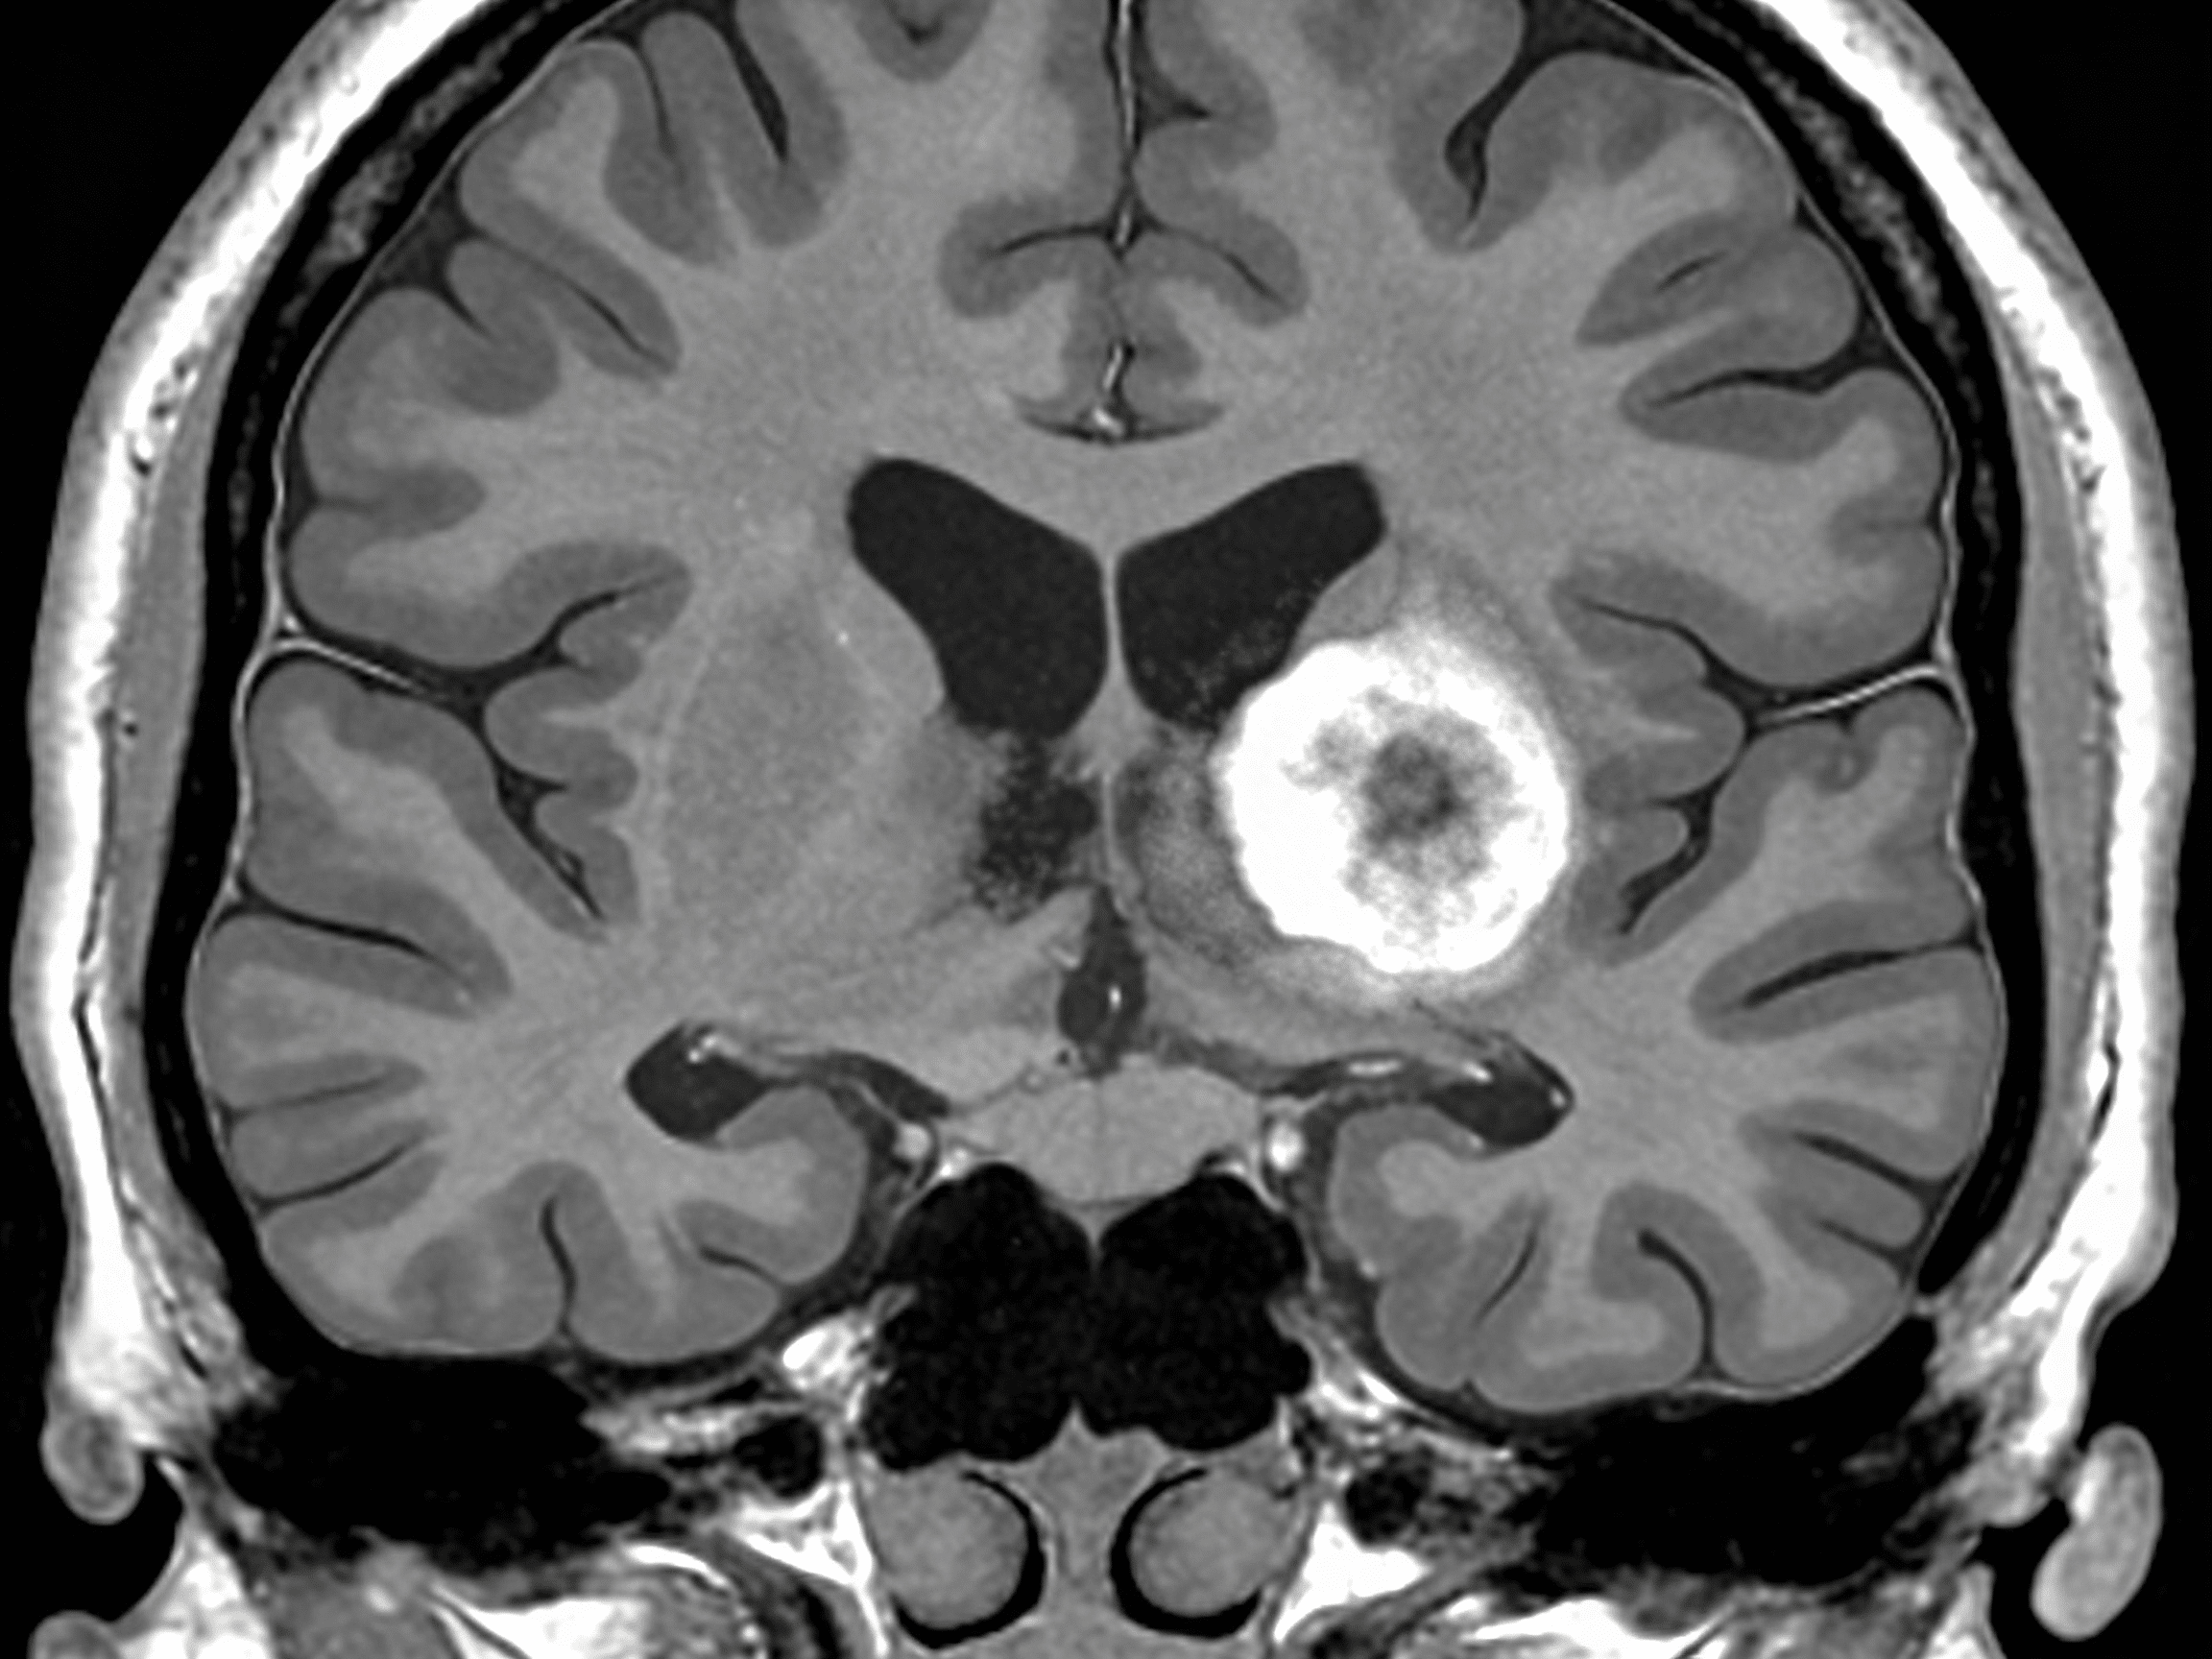

Priority ER's diagnostic capabilities for head CT for stroke, hemorrhage, or trauma exceed Joint Commission standards for emergency departments[14], featuring 64-slice CT scanner providing immediate high-resolution brain imaging identifying acute ischemic changes (loss of gray-white differentiation, hyperdense vessel sign), hemorrhagic stroke (hyperdense blood), skull fractures, and traumatic brain injuries within 10 minutes. Our emergency physicians trained in neuroimaging interpretation identify Alberta Stroke Program Early CT Score (ASPECTS) determining stroke severity, midline shift indicating mass effect, and hemorrhage volume calculating surgical urgency when neurosurgical intervention becomes necessary[15]. The integration of FAST (facial droop, arm weakness, speech difficulty, time) assessment, NIHSS scoring quantifying neurological deficit, and immediate treatment protocols ensures comprehensive stroke care from symptom recognition through definitive intervention.

Advanced imaging through our comprehensive diagnostic capabilities provides CT angiography visualizing arterial occlusions when mechanical thrombectomy candidates require transfer to comprehensive stroke centers, CT perfusion identifying ischemic penumbra (salvageable brain tissue) extending treatment windows beyond standard 4.5 hours, and repeat head CT performed 24 hours post-tPA monitoring for hemorrhagic transformation. For trauma patients, our emergency physicians utilize Canadian CT Head Rule and New Orleans Criteria determining which head injuries require imaging, preventing unnecessary radiation while ensuring dangerous bleeds aren't missed when clinical indicators mandate scanning. This comprehensive approach explains why the American Heart Association mandates door-to-CT time under 25 minutes for stroke patients, with Priority ER consistently achieving 10-minute door-to-scan times maximizing treatment eligibility.

What's the difference between ischemic and hemorrhagic stroke on head CT?

Ischemic strokes (87% of strokes) show early subtle changes including loss of gray-white differentiation and hyperdense vessel sign on head CT, caused by arterial blockage requiring tPA or thrombectomy. Hemorrhagic strokes (13%) show bright white blood on CT caused by arterial rupture, absolutely contraindicating tPA which would worsen bleeding causing death. Priority ER emergency physicians immediately differentiate stroke types using head CT, with ischemic strokes receiving clot-busting treatment while hemorrhagic strokes require blood pressure control and neurosurgical consultation for potential craniotomy.